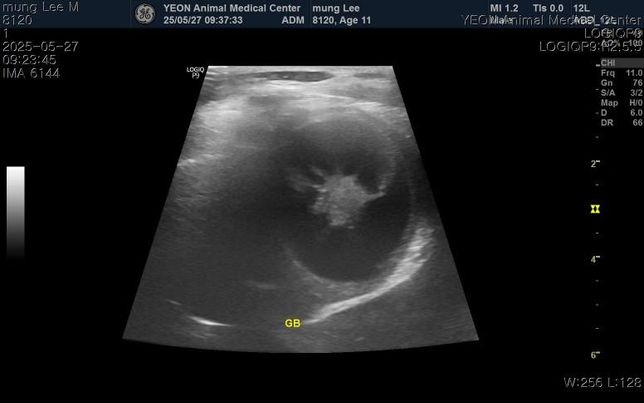

- 반려동물 건강반려동물매우진지한보더콜리강아지 담낭점액종 수술 없이 호전되기는 어려울까요?11살 4.7kg 포메 남아입니다.구토, 식욕저하, 기력저하로 내원해서 진료,검사 받아보니 염증, 간, 담낭 등 수치가 심하게 높다고 했고 빠른 입원치료와 담낭절제수술을 안내받았습니다.물만 먹어도 구토를해서 약도 못먹을것 같다하고.. 입원비와 수술비가 도저히 감당이 안될것 같은데 호전될 가능성이 전혀 없는걸까요?약물치료는 전혀 효과를 보지 못할까요?그리고 십이지장에 크론병?도 의심된다고 하는데 담낭 치료와는 치료방법이 상극이어서 담낭 먼저 제거하고 스테로이드치료가 필요하다고 안내받았습니다.자료 보시고 소견 말씀 부탁드립니다..1명의 전문가가 답변했어요